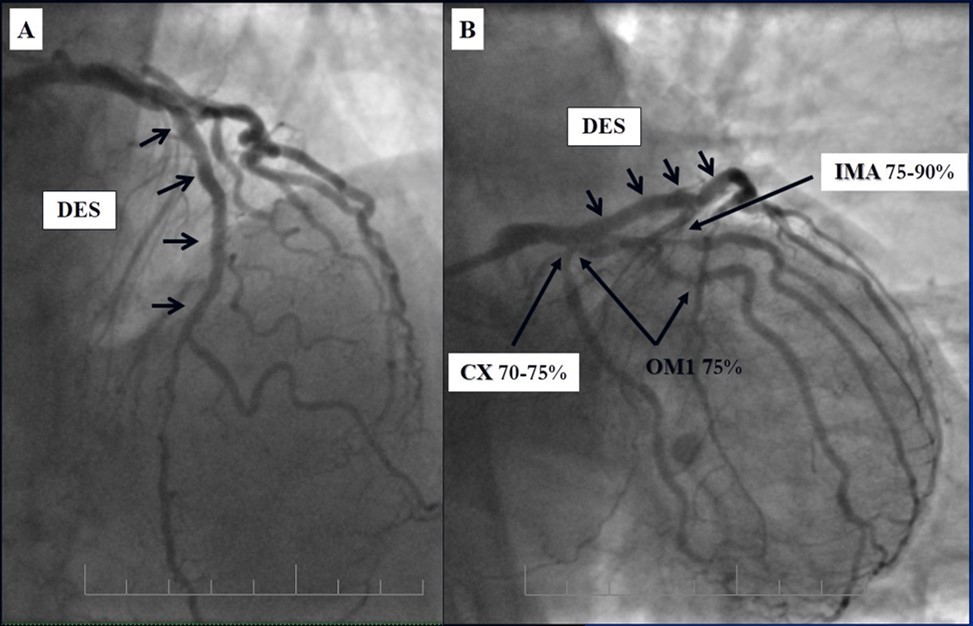

Angiography revealed rare anatomical variation LMCA quadrifurcation (Figure 1, Figure 2), 50% stenosis of the distal part of the LMCA, 40% stenosis of the ostial segment of left anterior descending (LAD) artery and diffuse prolonged 70-75-95% stenosis in mid-segment (Figure 3), 75% stenosis of the ostial segment of the circumflex (CX) artery, 75% stenosis of the ostial segment of the first marginal branch (OM1), 75-90% stenosis of the proximal segment of the intermediate artery (IMA), prolonged diffuse severe 90-95% stenosis of mid-segment of the right coronary artery (RCA) (Figure 4).

Figure 1.Quadrifurcation of the left main coronary artery

Figure 3.Prolonged diffuse severe 90-95% stenosis of mid-segment of the right coronary artery. A - Left anterior oblique 45° projection; B – Right anterior oblique 45° projection.

Figure 4.A - 50% stenosis of the distal segment of the LMCA; B - 70-75-95% stenosis in mid-segment of the LAD.